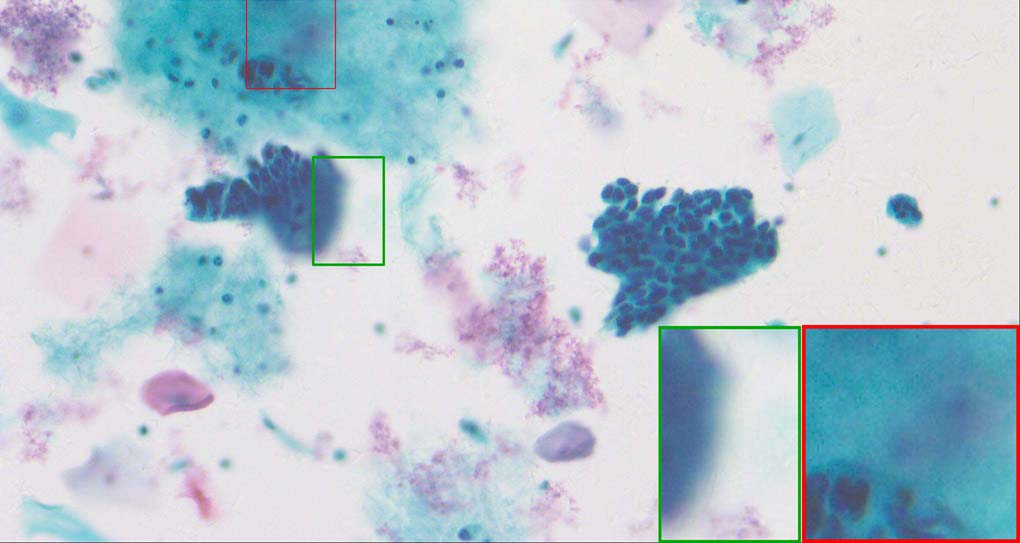

A good image fusion method should contain the following properties. First, it preserves both the details of small size objects and the integrity information of large size objects in the fused image, even in the case of the size of the interested objects varying largely in the image. For example, the cervical cell images from the microscope contain both small size isolated cells and large size agglomerates, which are both useful for cervical cytology [5]. Second, it should be efficient enough to handle large-scale data. For instance, it needs to process thousands of fields of view (FoV) in an acceptable time for the whole slide scanning in digital cytopathology [6], which requires to fuse a series of high resolution images captured at each FoV in a very efficient way. Third, it does not produce obvious artifacts. Despite being studied extensively, to our best knowledge, existing fusion methods may not meet these requirements simultaneously.

To demonstrate the effectiveness and efficiency of the proposed image fusion method , we conduct a set of comparative experiments on three image datasets. The first is composed by 8 pairs of multi-modal medical images and the second one contains 15 pairs of multi-focus gray or color natural images. These two datasets are often used in many related papers and some examples are shown in Figure 3(a) and Figure 3(b). The third one is a new multi-focus cervical cell image dataset collected by ourselves, which consists of 15 groups of color images and each group contains a series of multi-focus cervix cell images with size of or , etc. Some source examples are shown in Figure 3(c). Our source code implemented in C++ along with the new multi-focus cervical cell image dataset is available online.

Similarly, as shown in the close-up views of Figure 10, the fused images from DSIFT, IM, MWGF and BF are blurred and lose some nucleus details, while the results from DTCWT, GFF, CNN and NSCT produce halo artifacts. LP-SR based method can keep details well but also produces halo artifacts and other noise. Our method can preserve the focused areas of different source images well without introducing any artifacts. For the example illustrated in Figure 11, the fused images generated by DSIFT, DTCWT, IM and NSCT all fail to preserve the focused areas of different source images and result in extremely blurred images. The GFF, CNN, MWGF and BF based method introduces a lot of color distortion of the nucleus regions and the obvious halo artifact. The result of LP-SR based method is close to the one of our method but introduces some odd color distortion. Again, our method produces fused image which can preserve the focused areas of different source images well without introducing any artifacts.